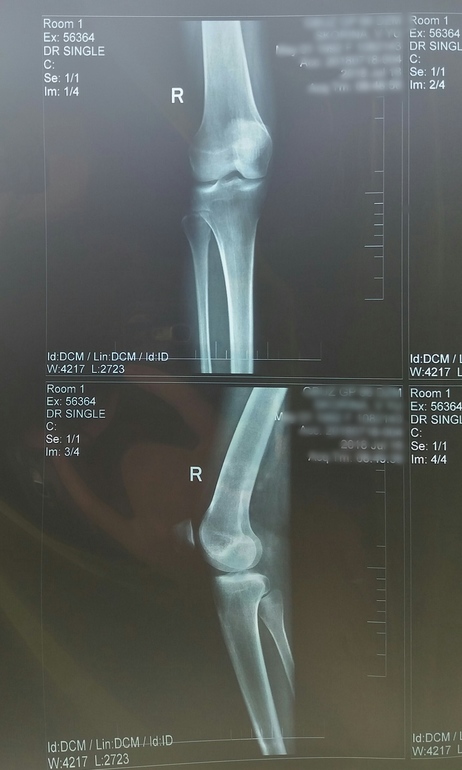

Гонартроз и остеофиты

Опорно-двигательный аппаратСделала снимок, к ортопеду 2 августа только. У кого-нибудь есть похожие проблемы? Как лечились, лекарства или операцией? Вдруг кто-нибудь понимает, насколько у меня всё плохо, снимок под кат

Я в снимках не разбираюсь, но у меня гонартроз коленных суставов 3 степени. Об операции пока не говорят, но очень настаивают на внутрисуставных уколах гиалуроновой кислоты. Я пока не соглашаюсь потому что во-первых не всем помогает, а во-вторых организм все таки должен сам восстанавливаться. А если колоть начать, то другое уже и не поможет. Огромные деньги стоит.